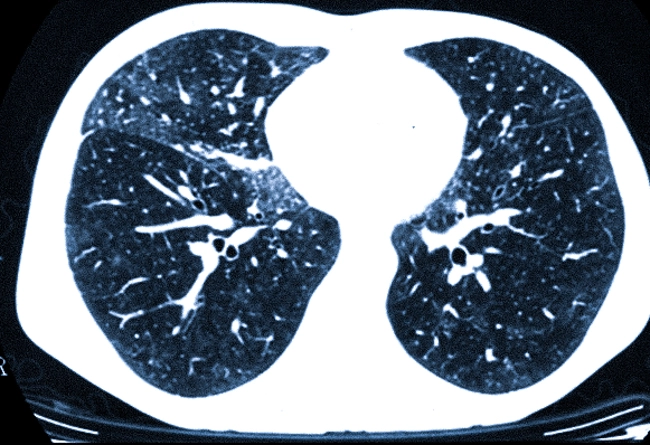

Идиопатический легочный фиброз

Это прогрессирующее заболевание легких, характеризующееся образованием рубцовой ткани, что приводит к необратимому нарушению обмена газов. По мере прогрессирования болезни гипоксемия становится более выраженной, требуя постоянной подачи дополнительного кислорода для поддержания адекватной функции органов и уменьшения симптомов.